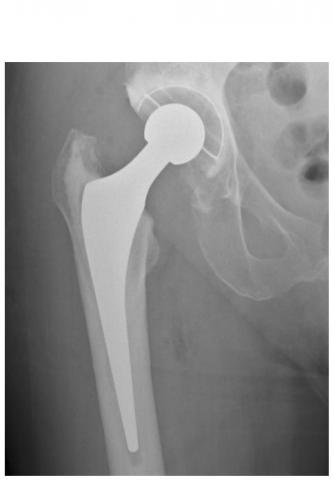

ARTHROPLASTIE de la HANCHE et du GENOU : Un taux de réussite élevé, un résultat durable

80% des arthroplasties du genou et 60% des arthroplasties de la hanche sont toujours en place après 25 ans.

Cette intervention désormais classique permettant de rétablir la forme et la mobilité d'une articulation abîmée ou bloquée, que ce soit l’articulation de la hanche ou du genou, atteint aujourd’hui un taux de réussite élevé, conclut cet examen et cette méta-analyse de la littérature. L’équipe de l’Université de Bristol, après avoir examiné des milliers d'études de cas remontant à 25 ans dans 6 pays, estime pour la première fois la durée probable de ces arthroplasties : 80% des arthroplasties du genou et 60% des arthroplasties de la hanche sont toujours en place après 25 ans. Des données très rassurantes, présentées dans le Lancet.

Des variations considérables en fonction des types d’arthroplasties : un remplacement de la hanche comprend principalement 2 composants (col, cavité) mais reste variable dans la manière dont ces pièces sont fixées à l'os, ainsi que dans les matériaux utilisés pour consolider la surface d'appui. Idem pour l’arthroplastie du genou, l’arthroplastie totale va remplacer toute la surface articulaire du patient, tandis qu'une prothèse de genou unicondylienne ne remplace que la partie endommagée du genou. Bref, les variations sont considérables en matière d’arthroplasties de la hanche et du genou, cependant ces facteurs ont bien été pris en compte dans l’analyse.